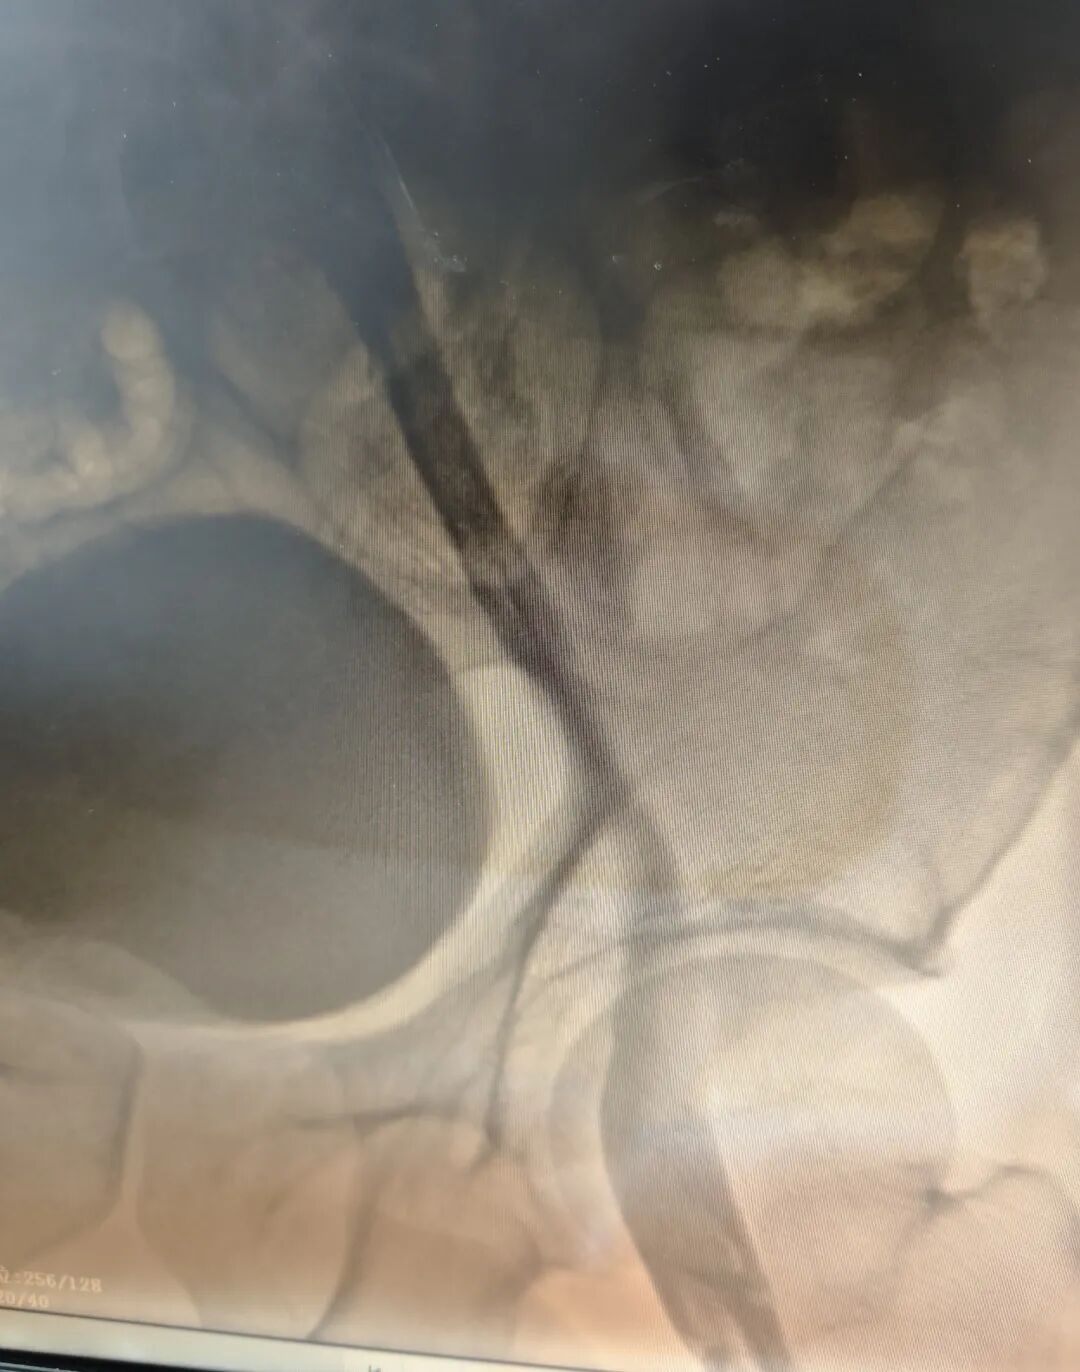

术后造影

田明主任精准操作,经鞘管将静脉取栓支架推送至髂总静脉,并一路延伸至股浅静脉,通过四次小心翼翼的反复拉栓,成功清除大量血栓。最终,复查造影传来捷报:患者股浅静脉、髂静脉及股静脉血流通畅,未见残余血栓,手术获得圆满成功!这一结果让手术室里的所有人都松了一口气,也意味着这场与病魔的激烈较量取得了阶段性的胜利。